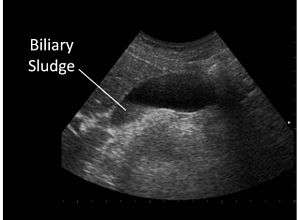

Biliary sludge

Biliary sludge in gallbladder on ultrasound | |

Biliary sludge is typically diagnosed by CT scan, transabdominal ultrasonography.[1][2] Endoscopic ultrasonography is another more sensitive option. However, the gold standard is considered to be direct microscopy of aspirated gallbladder bile.[1][2] This method is much more sensitive, although it is less practical.[2]